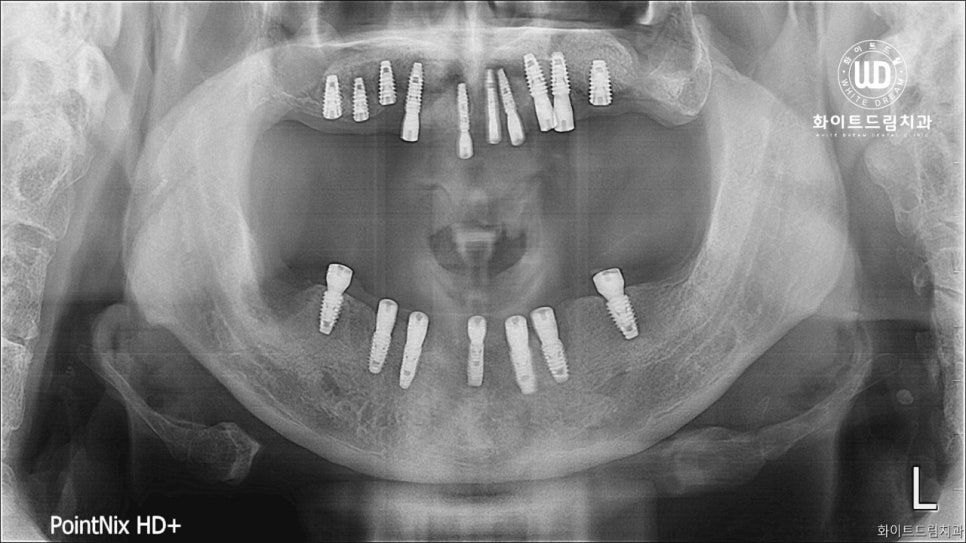

다음은 상악동 거상술과 치조골이식술을 동반한 임플란트 식립 후 최종 진단 결과물입니다.

좌측에 보이는 사진이 임플란트 치료 전 모습이며, 우측이 치료 후 모습입니다.

이전의 구강상태와 확연한 차이를 보이고, 구강 저작력이 크게 향상되는 등 만족스러운 결과가 나왔습니다.

치료가 완료된 사진을 살펴보면 임플란트가 뿌리부터 머리까지 나란히 매끄럽게 연결되어 있는 것을 확인하실 수 있는데, 상악 하악의 U자 형태가 본 케이스와 같이 나올 수 있으려면 임플란트 보철 식립 방향을 잘 체크해야합니다.

환자분께서 부분틀니를 사용하다가 전체 임플란트를 진행하게 됐는데, 훨씬 더 편안하고 음식을 씹는데 큰 문제가 없어 만족한다는 말씀을 전해주신 것이 기억에 남습니다.